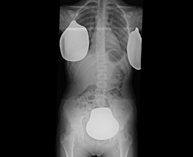

- RX Abdomen

Técnica mediante la cual, utilizando rayos X, se obtienen imágenes del abdomen (estómago, intestino delgado, intestino grueso, hígado, riñones, vejiga, pelvis ósea, etc.) para su estudio.